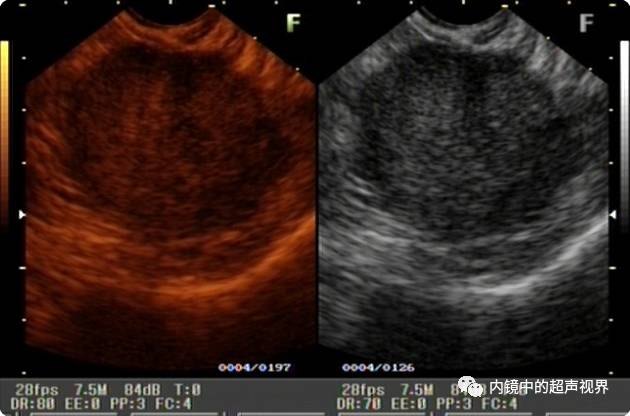

再来一纵隔肿物的图片,是DR30和80的对比,很明显。

纵隔肿物